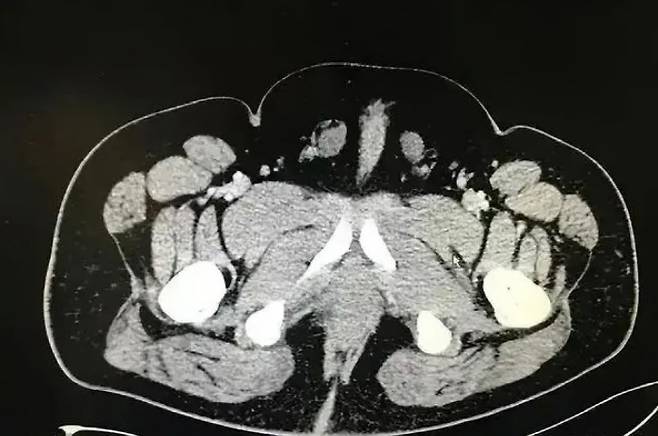

인터섹스는 성적 발달 장애(DSD, Disorders of sexual development)를 이르는 것으로 염색체나 생식기, 호르몬, 내부 생식기관이 남성이나 여성이라는 이분법적 구조에 맞지 않는 특성을 하나 이상 가지고 태어난 상태를 말한다.